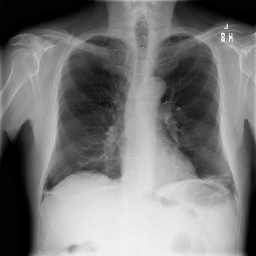

• Chest X-ray Dataset (CXR) [34]: This dataset originates from the NIH, which is the largest chest radiograph data set. From 30,805 special patients, 112,120 frontal X-ray images are collected. Each X-ray is linked to the associated text disease label, which is drawn from the relevant radiological reports using an NLP algorithm.

The proposed QMedShield’s security is evaluated using a number of metrics and proved that it is resistant to various cryptographic attacks including brute-force attacks, statistical attacks, histogram attacks, and differential attacks. Throughout the section, 6 sample medical images BMRI1,BMRI2,CXR1,CXR2,LCT1,LCT2𝐵𝑀𝑅subscript𝐼1𝐵𝑀𝑅subscript𝐼2𝐶𝑋subscript𝑅1𝐶𝑋subscript𝑅2𝐿𝐶subscript𝑇1𝐿𝐶subscript𝑇2BMRI_{1},BMRI_{2},CXR_{1},CXR_{2},LCT_{1},LCT_{2} are taken (2 images from each dataset) to show the performance comparison. The selection of MRI, X-ray, and CT images for the encryption task aims to demonstrate the versatility and effectiveness of our model across various imaging modalities, showcasing its applicability and robustness in diverse clinical scenarios. Figure 11 shows the selected sample medical images and their corresponding encrypted images.

Refer to caption

(a) BMRI1𝐵𝑀𝑅subscript𝐼1BMRI_{1}

(b) CXR1𝐶𝑋subscript𝑅1CXR_{1}

(c) LCT1𝐿𝐶subscript𝑇1LCT_{1}

(d) BMRI2𝐵𝑀𝑅subscript𝐼2BMRI_{2}

(e) CXR2𝐶𝑋subscript𝑅2CXR_{2}

(f) LCT2𝐿𝐶subscript𝑇2LCT_{2}

(g) E(BMRI1)𝐸𝐵𝑀𝑅subscript𝐼1E(BMRI_{1})

(h) E(CXR1)𝐸𝐶𝑋subscript𝑅1E(CXR_{1})

(i) E(LCT1)𝐸𝐿𝐶subscript𝑇1E(LCT_{1})

(j) E(BMRI2)𝐸𝐵𝑀𝑅subscript𝐼2E(BMRI_{2})

(k) E(CXR2)𝐸𝐶𝑋subscript𝑅2E(CXR_{2})

(l) E(LCT2)𝐸𝐿𝐶subscript𝑇2E(LCT_{2})

Figure 11: Selected sample plain medical images and the corresponding encrypted cipher images